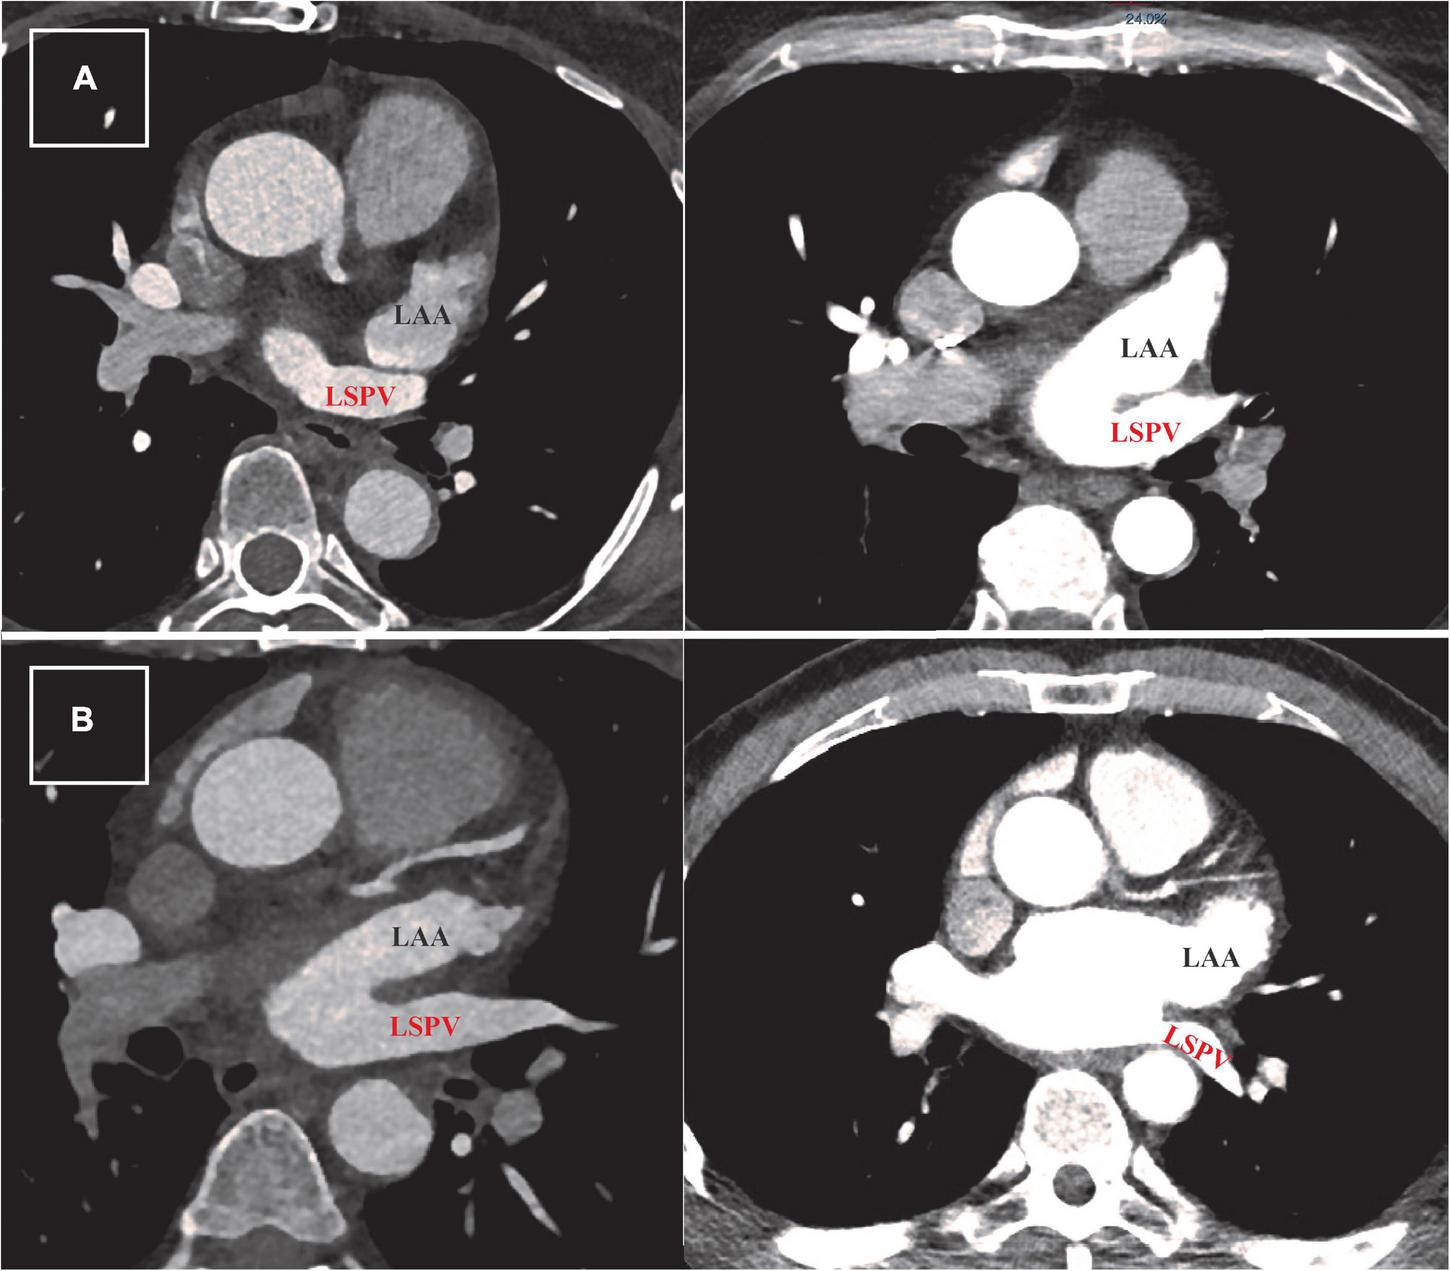

Our standard scan acquisition protocol consists of a high-pitch acquisition in the arterial phase covering at least the LA and a delayed phase high-pitch acquisition of at least the LAA. CT angiography examinations were performed with a 384-slice scanner (SIEMENS SOMATOM Force, Siemens Healthlineers) with prospective electrocardiogram (ECG)-triggered axial acquisition mode. For cardiac CT, 80–100 kV with 200–300°mAs tube current was used based on patient anthropometrics. Image acquisition was performed with 2 mm × 192 mm × 0.6 mm detector collimation and 0.25 s gantry rotation time. Heart rate control medication was not routinely administered prior to scanning. Contrast material was injected with a flow rate of 4.5–5.5 ml/s through antecubital vein access via 18-gauge peripheral IV using a four-phasic protocol. Bolus tracking in the LA was used to obtain the proper scan timing. CT datasets were reconstructed with 0.6-mm slice thickness with 0.4 mm increments. We examined LAA morphology classification, the approximate LAA length, diameters of the LAA ostium (axial, coronal, and sagittal plane), LAA shape, and relationship of the LAA to the left superior pulmonary vein (LSPV). The spatial relationship between LAA and LSPV was determined using two-dimensional axial CT images. Abutting LAA–LSPV was defined as cases when the LSPV touched the posterior aspect of LAA, and the maximal distance between the two structures was less than 2 mm (Figure 1A). Those cases where the distance between LAA and LSPV was more than 2 mm were defined as non-abutting LAA-LSPV (Figure 1B). CT scans were examined, and measurements were made by two-blinded observers (NS and JS).

FIGURE 1

Defining abutting and non-abutting left atrial appendage–left superior pulmonary vein (LAA-LSPV). (A) Two examples of cardiac computed tomography (CT) scans from patients with abutting LAA (written in black) and LSPV (written in red). The measured distance between LAA and LSPV in these cases was less than 2 mm. (B) Two examples of CT scans from patients with persistent atrial fibrillation showing different trajectory of non-abutting LAA and LSPV. The measured distance between these two structures was more than 2 mm in both patients.